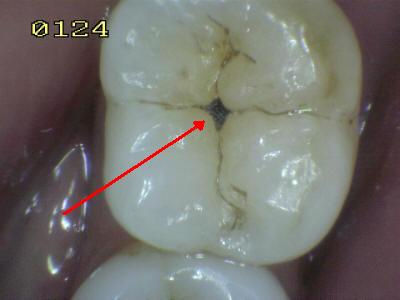

El

cepillado no llega a eliminar las bacterias que se alojan en los

surcos y fosas de premolares y molares. Comenzando el

proceso de desmineralización (Ver secuencia derecha) y creando

una cavidad que compromete la integridad dental. (Ver imagen

izquierda) La evolución

de este tipo de lesión es de solo un par de meses. |